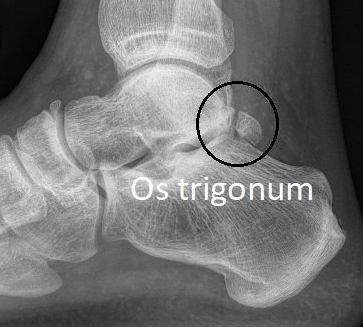

- 5% of people are born with an extra bone at the back of the ankle called an os trigonum. This makes posterior impingement more likely.

- investigations (X-ray, CT or MRI).

These investigations determine if the impingement is due to bone spurs, loose bone fragments, arthritis or just soft tissue scarring.